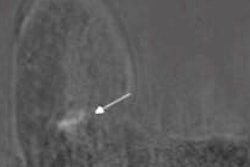

Overall, the Swiss authors report that magnetic markers are widely visible on MRI images due to the susceptibility artifact that they generate.

"However, the same artifact that accounts for visibility of the marker can possibly mask or mimic, depending on the circumstances, a residual tumoral enhancement and thus reduce the diagnostic accuracy of MRI," they wrote. "Indeed, the size and appearance of metallic artifact on MRI depends on several factors, namely the material of the clip (in particular its magnetic susceptibility), the magnetic field strength of the system, and the sequence itself (gradient echo or spin echo are not equally sensitive to the presence of metal)."